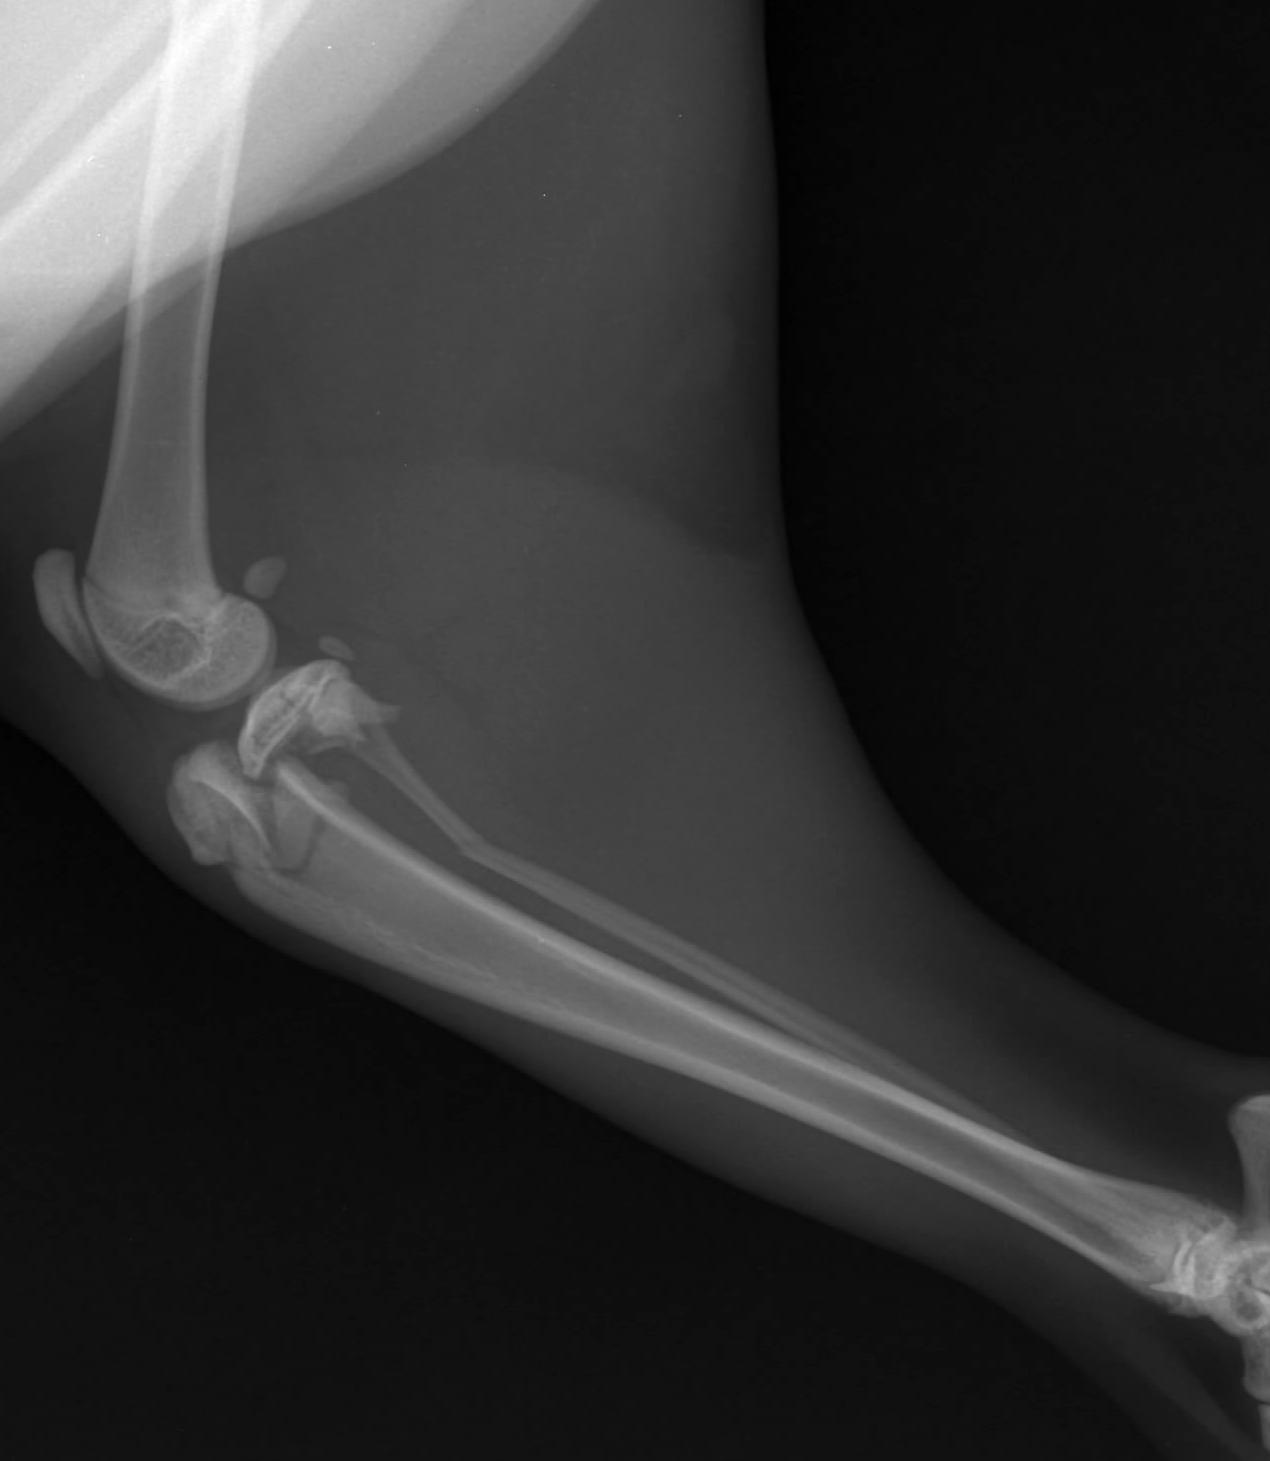

Vena cefalică plasată pe fața medială a antebrațului, superficial de fascia antebrahială, prezintă un traiect oblic în sens dorso-cranial, până la inserția distală a mușchiului biceps, unde primește afluența venei cefalice accesorii 5 (figura 10). Poziția venei cefalice a fost luată în considerare pentru crearea abordului la radius atât în accesul proximal, cât și în cel distal. Validarea poziționării corecte a plăcii în raport cu osul și selecția adecvată a dimensiunii și numărului șuruburilor s-a realizat prin examenul imagistic radiografic convențional, utilizând incidențele clasice, respectiv incidența medio-laterală și incidența cranio-caudală, prezentate în figura 11a și b. Investigațiile imagistice postintervenție au relevat că spațiile articulare humero-radio-ulnar și carpo-radio-ulnar nu au fost modificate. Atât proximal, cât și distal, metafizele, epifizele și cartilajele articu -

lare au rămas integre. Caracteristicile spațiului interosos radio-ulnar nu au fost modificate de aplicarea plăcii și a șuruburilor. Am procedat la înlocuirea abordul clasic cranial pe radius cu unul cranio-medial. Explicația selecției acestei căi de acces la radius derivă din unul dintre principiile MIPO conform căreia șuruburile trebuie să fie amplasate cât

și incidență cranio-caudală (b)

mai proximal, respectiv cât mai distal pentru a crește raportul de sprijin al implantului (ideal ar fi ca placa să fie plasată de pe metafiză proximală pe metafiză distală).